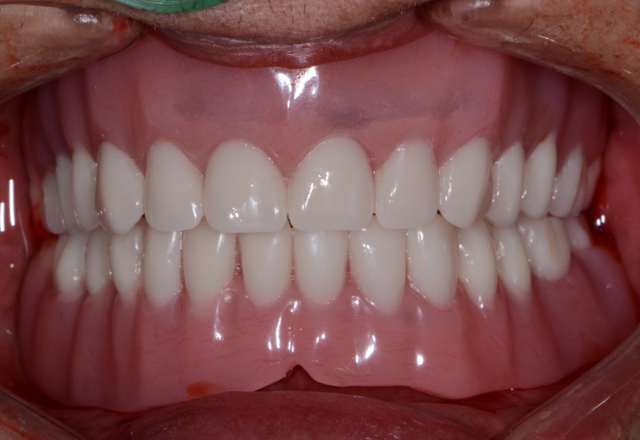

The first step was to brush a thin coat of adhesive into the overdenture recesses (Fig. 14) to enhance retention between the denture base and the hard reline material. Petroleum jelly was applied to the surrounding surfaces of the denture to prevent unwanted adherence of excess material. Once mixed, the Rebase II material (Figs. 15 & 16) was placed into a plastic dispensing syringe and injected up to two-thirds the height of each recess as well as on to the attachments. During seating, the prosthesis was gently held in place by hand. After a total of about three minutes, the overdenture with the incorporated retention caps was removed. Any excess material was removed with a trimming bur (Fig. 17). At the completion of the prosthetic phase, the patient stated how pleased she was to be able to smile and function without the prosthesis wobbling or falling out (Fig. 18). Most importantly from a clinical standpoint, we were pleased to see the areas in the upper and lower arches healthy and infection-free.

Fig. 17 Fig. 18